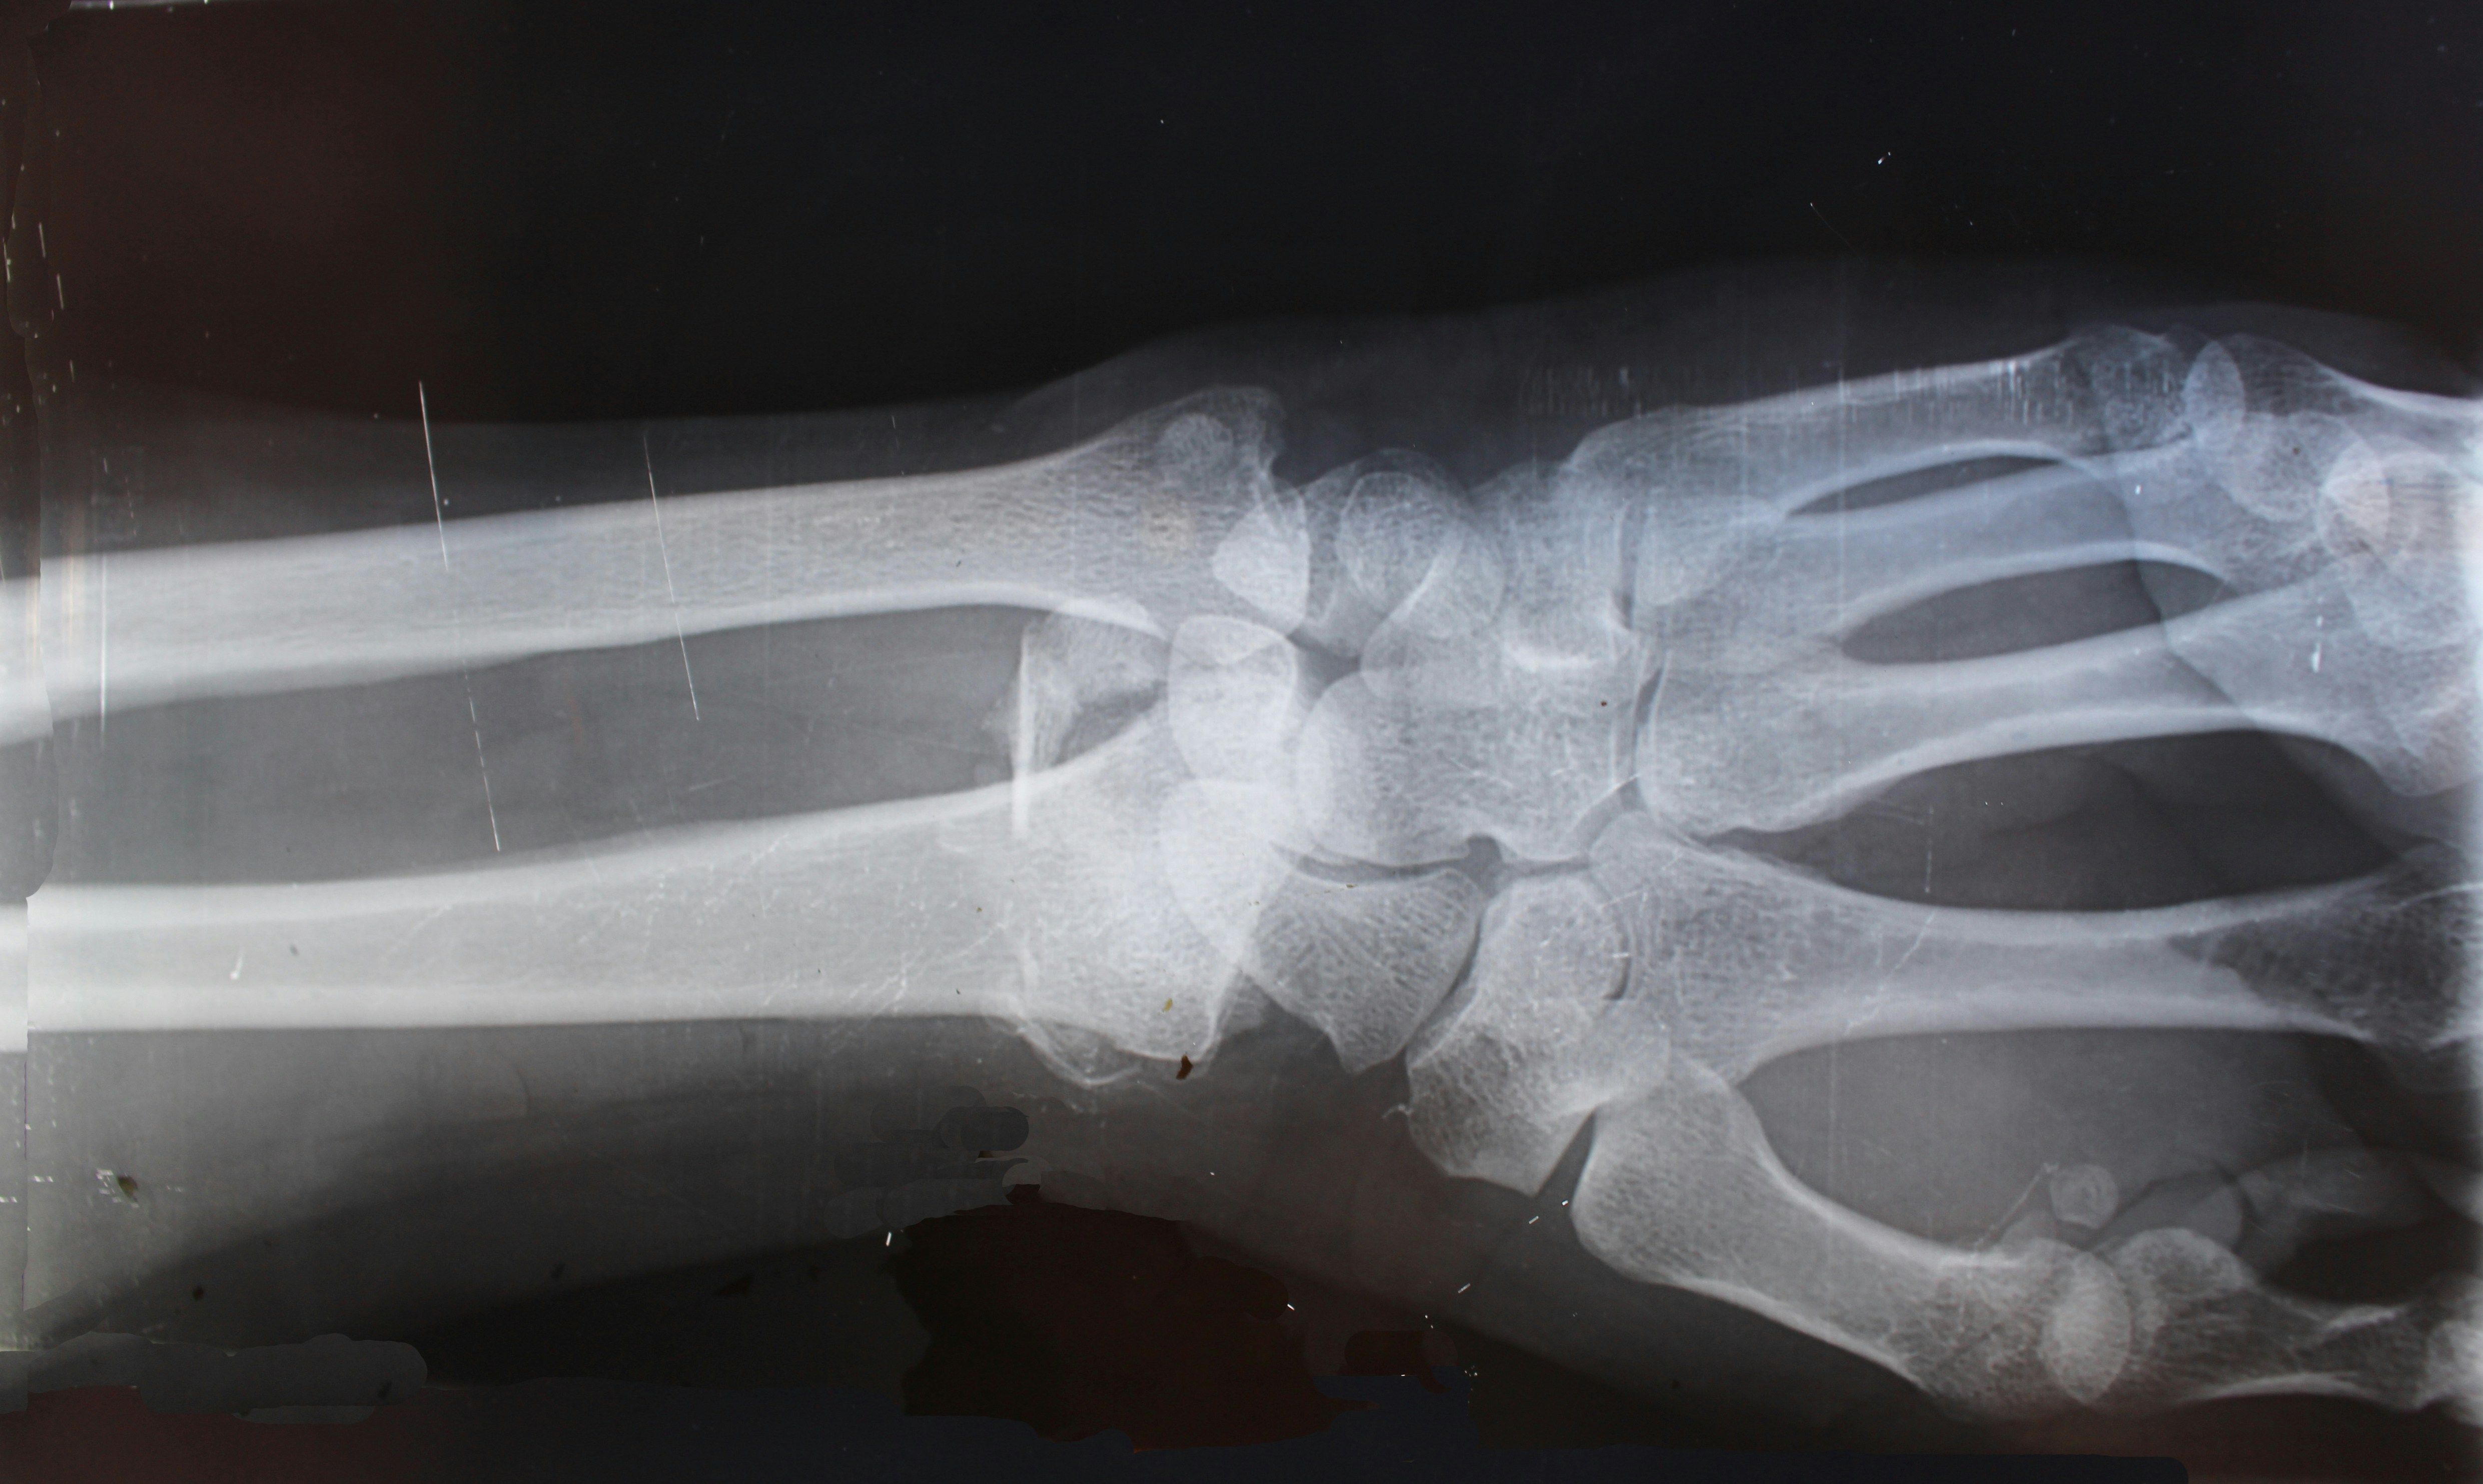

가장 흔한 원인은 관절을 보호하고 있는 **연골의 마모**입니다. 오랜 시간 관절을 사용하면서 연골이 얇아지고 뼈와 뼈가 직접 부딪히게 되는데, 이때 극심한 통증과 부종이 발생합니다. 주로 체중 부하가 큰 무릎이나 고관절, 손가락 끝마디에 자주 나타나며 저녁 시간대에 통증이 심해지는 특징이 있습니다.

퇴행성과 달리 류마티스는 **내 몸의 면역 세포가 관절 활막을 공격**하여 생기는 자가면역 질환입니다. 아침에 일어났을 때 관절이 뻣뻣하게 굳는 '조조강직' 현상이 1시간 이상 지속된다면 이를 의심해봐야 합니다. 손가락 중간 마디나 손목처럼 작은 관절에서 양측 대칭으로 나타나는 것이 특징입니다.